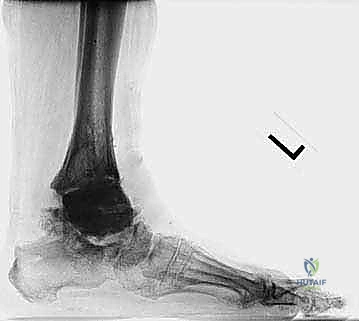

FIG 1 • Acute ( A ) and chronic ( B ) medial malleolus fractures. The former fractures occur due to an intraoperative technical error.

* Late (Chronic): Result from weakened bone architecture due to osteolytic cysts, or undue stresses applied to the malleoli from deformity or altered gait mechanics. Micro- or macromotion at the prosthesis-bone interface, particularly at the fibula, can also contribute.

FIG 1 • Acute ( A ) and chronic ( B ) medial malleolus fractures. The latter can occur from imbalance about the prosthesis with undue stresses.

The natural history of malleolar fractures is compromised by the limited bone available due to the prior implant. This reduces the surface area for healing, increasing the likelihood of nonunion. Nonunion can lead to a relative increase in malleolar length and subsequent ligamentous laxity, predisposing to instability and deformity. Once deformity is present, it creates abnormal stresses that further hinder union.